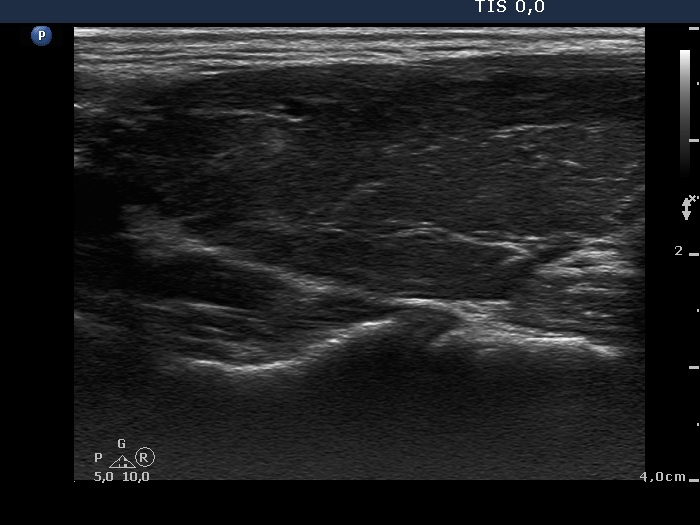

Consecutive patients with the final diagnosis of Hashimoto's thyroiditis - case 32 (717) (ultrasonographic picture 6)

Left lobe, longitudinal scan.